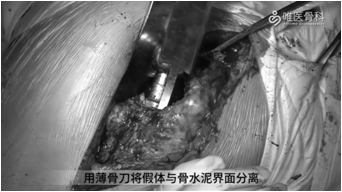

取出股骨假体:用骨刀去除假体近端周围的覆盖骨,使假体颈领充分显露,再用薄骨刀将假体与骨水泥界面进行分离。然后采用股骨假体专用工具取出假体,本病例采用音叉很容易就将假体取出。